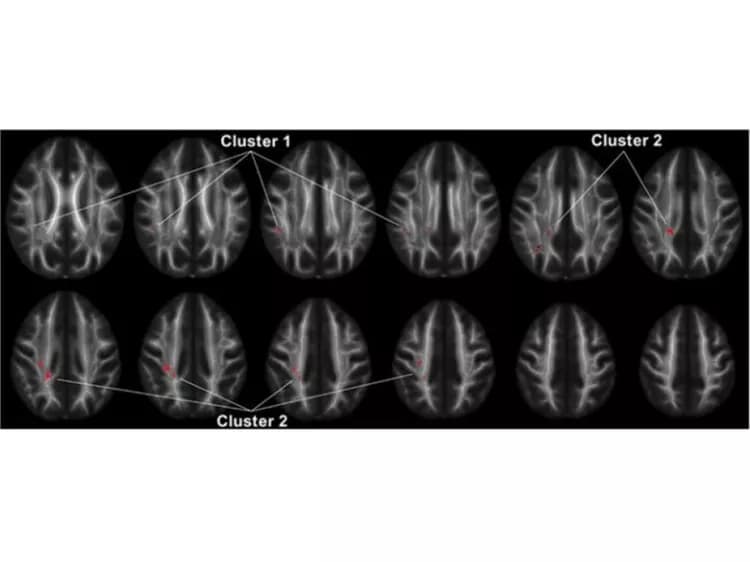

In a new study published in the journal Neuropsychopharmacology, neuroscientists from the University of Chicago show that white matter in a region of the brain called the superior longitudinal fasciculus (SLF) has less integrity and density in people with IED than in healthy individuals and those with other psychiatric disorders. The SLF connects the brain's frontal lobe--responsible for decision-making, emotion and understanding consequences of actions--with the parietal lobe, which processes language and sensory input.

Lee and his colleagues, including senior author Emil Coccaro, MD, Ellen C. Manning Professor and Chair of Psychiatry and Behavioral Neuroscience at UChicago, used diffusion tensor imaging, a form of magnetic resonance imaging (MRI) that measures the volume and density of white matter connective tissue in the brain. Connectivity is a critical issue because the brains of people with psychiatric disorders usually show very few physical differences from healthy individuals.

Decreased connectivity between regions of the brain that process a social situation could lead to the impaired judgment that escalates to an explosive outburst of anger. The discovery of connectivity deficits in a specific region of the brain like the SLF provides an important starting point for more research on people with IED, as well as those with borderline personality disorder, who share similar social and emotional problems and appear to have the same abnormality in the SLF.